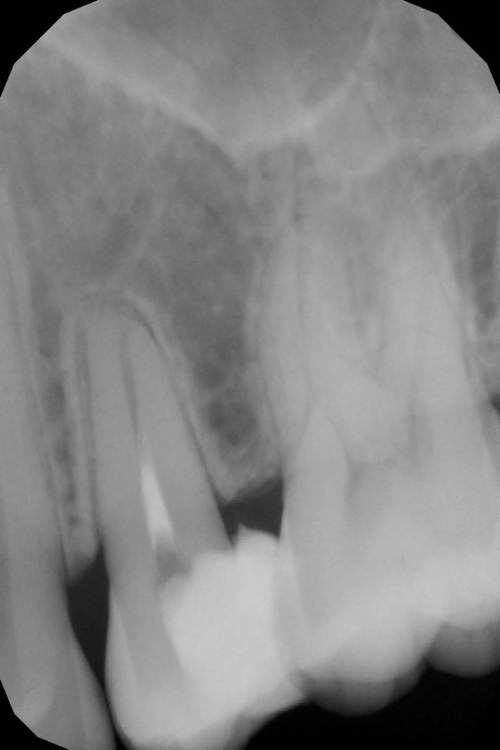

Гарриевич Опубликовано 21 мая, 2022 Поделиться Опубликовано 21 мая, 2022 (изменено) Будущее за регенеративной эндодонтией?) лечение в 2 посещения из-за нехватки времени (новый ассистент, перегруз пациентами, мысли о поднятии стоимости лечения, гипердиагностика?) глубокая пульпотомия, триоксидент, композит. фото подробно выложил это снимок с временной пломбой мало ли что вы подумаете Изменено 21 мая, 2022 пользователем Гарриевич 1 Ссылка на комментарий

ЛанаМ Опубликовано 23 мая, 2022 Поделиться Опубликовано 23 мая, 2022 Показаниями к пульпотомии является острый очаговый пульпит, а судя по снимку там хронический пульпит + хронический фиброзный периодонтит. Я бы выбрала пульпэктомию. 1 1 Ссылка на комментарий

Гарриевич Опубликовано 23 мая, 2022 Автор Поделиться Опубликовано 23 мая, 2022 13 часов назад, ЛанаМ сказал: Показаниями к пульпотомии является острый очаговый пульпит, а судя по снимку там хронический пульпит + хронический фиброзный периодонтит. Я бы выбрала пульпэктомию. Спасибо за мнение, но Зуб адекватно реагировал на холодовой раздражитель Скрытия произошло в момент препарирования полости Ссылка на комментарий